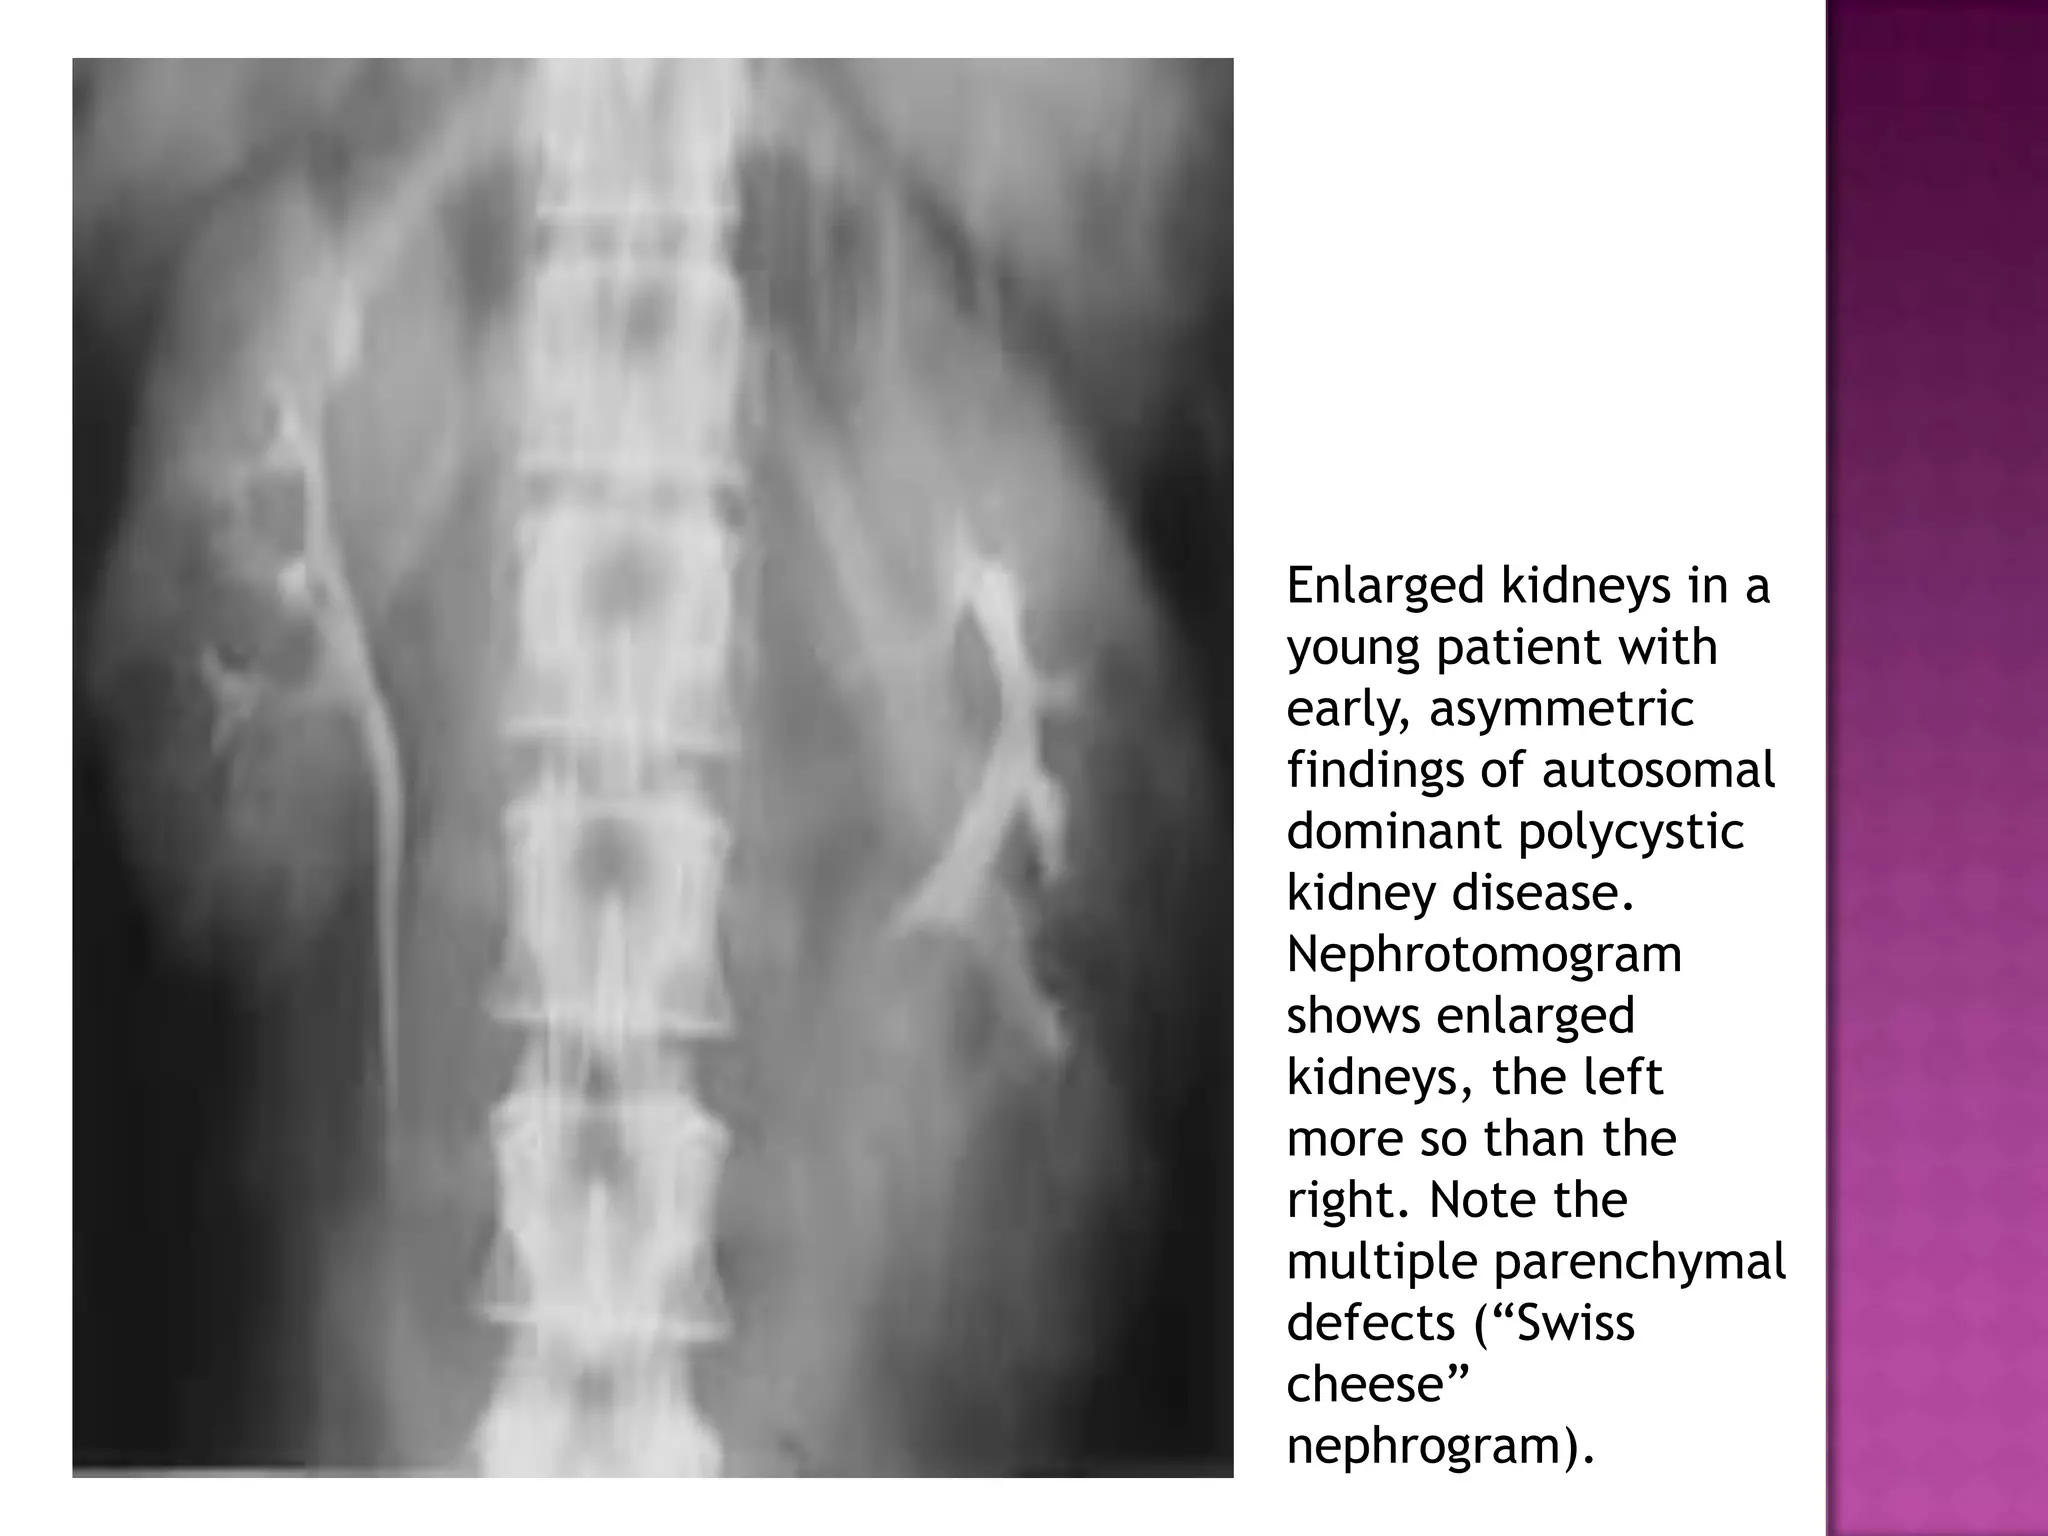

Enlarged kidneys in a

young patient with

early, asymmetric

findings of autosomal

dominant polycystic

kidney disease.

Nephrotomogram

shows enlarged

kidneys, the left

more so than the

right. Note the

multiple parenchymal

defects (“Swiss

cheese”

nephrogram).

Enlarged kidneys ina young patient with early, asymmetric findings of autosomal dominant polycystic kidney disease. Nephrotomogram shows enlarged kidneys, the left more so than the right. Note the multiple parenchymal defects (“Swiss cheese” nephrogram).